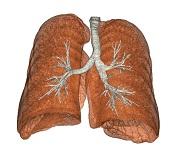

Lung and Airway Segmentations

Emphysema Detection and Quantification